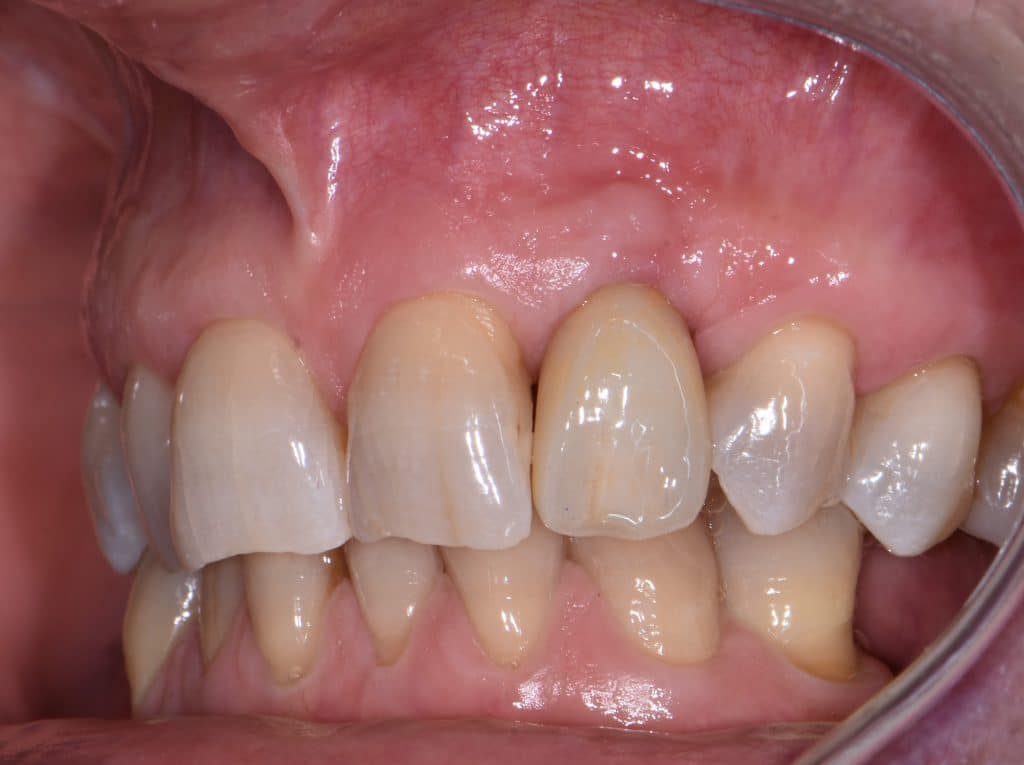

La pz N.G. di anni 52 (ASA 1) viene visitata nel mese di settembre 2017 per la mobilità ed inestetismo dell’elemento protesico 22, (foto iniziali sequenza 1) si evidenzia una frattura parziale della radice, si decide per l’estrazione ( foto sequenza 2) e sostituzione dell’elemento con un restauro implanto-protesico. Purtroppo la scarsa quota ossea apicale all’alveolo post-estrattivo (foto 2 rx) e l’alta valenza estetica dell’elemento ci rende cauti e si programma una socket preservation post estrattiva con l’ausilio delle membrane di prf (foto prf e socket sequenza 3 e 4). Durente i 5 mesi di guarigione la pz porta una protesi parziale mobile (foto 5,2) , a guarigione del sito post estrattivo si evidenzia una buona conservazione dei volumi osseo-gengivali,(foto guarigione sequenza 6) se pur presente una recessione distale all’elemnto 21.Nel mese di febbraio 2018 si procede all’inserimento di un impianto max-stability 3,75x12mm disegnando un lembo anticipato palatino per consentire un aumento dei tessuti vestibolari suturando con tecnica rool flap e trasformando l’elemento parziale mobile in una corona singola a carico immediato sul moncone temporameo applicando i concetti protesici bopt , (foto impianto moncone protesi provvisoria sequenza foto 7-8-9). Durante il periodo di maturazione dei tessuti molli vengono apportate opportune modifiche ai profili del provvisorio al fine di dare maggior spazio al tessuto gengivale, ( fotosequenza 10).Dopo circa 2 mesi dal protesizzazione provvisoria si è proceduto alla realizzazione del manufatto protesico con tecnica chair side sirona con l’ausilio del t-base (foto sequenza 11-12-13), realizzando in una sola seduta una corona in disilicato, ottenendo un risultato più che soddisfacente (Foto 14). Nel controllo a 3 mesi dal carico definitivo si apprezza la perfetta conservazione dei livelli ossei e gengivali. (foto sequenza 15).concludo con un follow up a 18 . Tengo a sottolineare che un caso come questo è stato conducibile con buoni risultati solo grazie alla piena fiducia della pz e alla sua massima motivazione e collaborazione. Ad oggi la pz sorride soddisfatta del risultato. E questo rappresenta la massima ricompensa di chi dedica tutto se stesso alla professione.